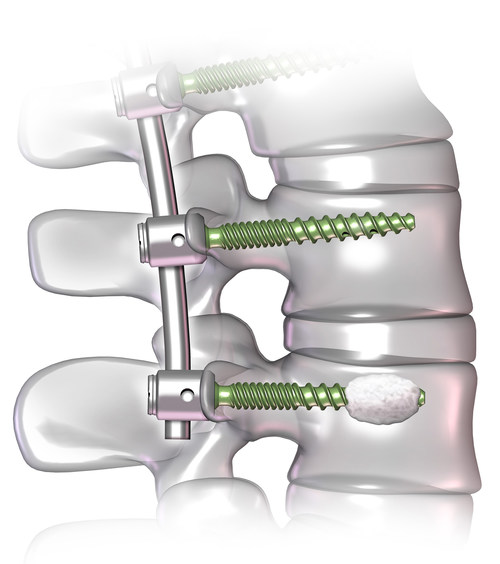

(PDF) USS Variable Axis Screw (VAS) System Metaphyseal Screw Synthes The 2.7 mm/3.5 mm va lcp™ ankle trauma system is a comprehensive plating system that merges variable angle locking screw technology with conventional. Use the lcp metaphyseal plate according to the lcp principles (see lcp instructions for use, art. 6 synthes lcp locking compression plate ordering information basic lcp plates lcp metaphyseal plates 3.5 steel. Original instruments and implants of. Metaphyseal Screw Synthes.